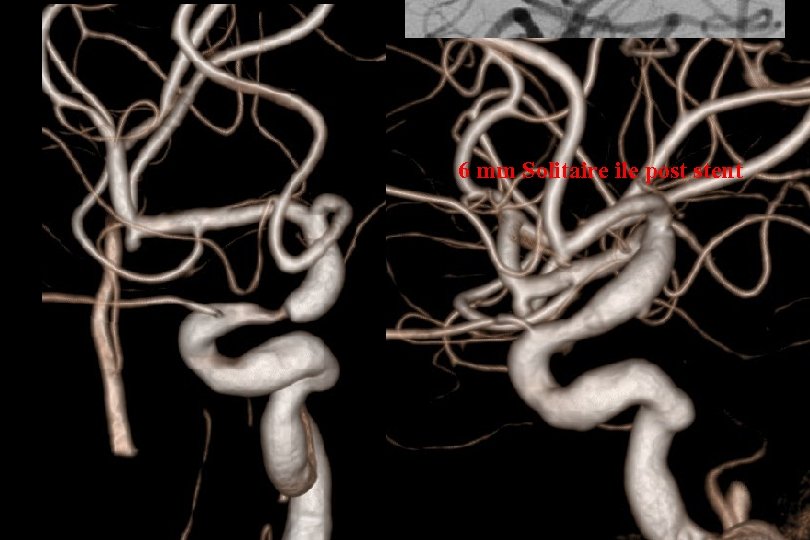

66 mm Solitaire ile post stent